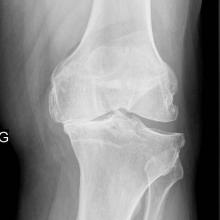

The diabetes drug metformin provided overweight/obese patients with osteoarthritis (OA) of the knee with significantly greater pain relief than did placebo in a small randomized trial, researchers said.